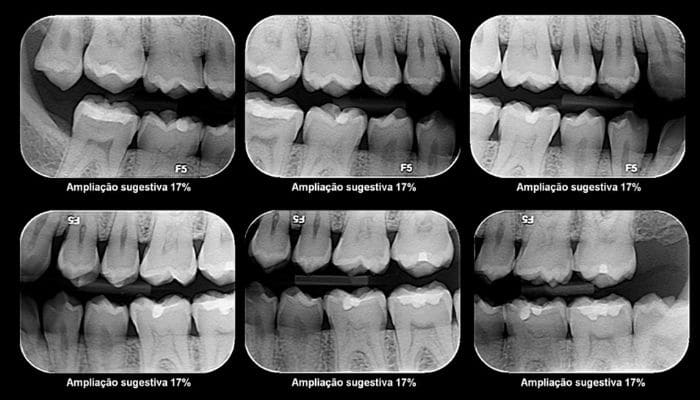

1 – Extrações Simples – dentes extraídos devido a cáries, infecções ou problemas ortodônticos.

2 – Extrações Cirúrgicas – remoção de dentes impactados, que não conseguem emergir normalmente.

3 – Extrações de Dentes do Siso – remoção dos dentes terceiros molares, frequentemente devido a problemas de espaço ou impactação.

4 – Extrações de Pré-Molares para Ortodontia – remoção seletiva de pré-molares pode ser realizada para criar espaço para o tratamento ortodôntico